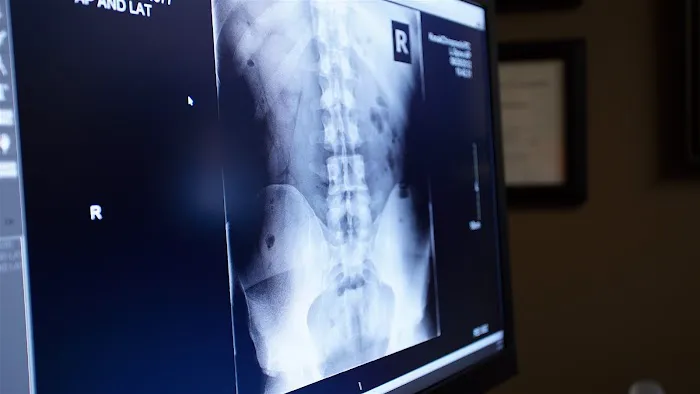

Chiropractic Adjustments: At the core of their practice, Dr. Kevin Kosak utilizes various techniques, including Diversified Technique, Applied Kinesiology (AK), Thompson Drop Technique, and Kale Upper Cervical Technique. These adjustments are designed to correct spinal and extremity misalignments, reduce nerve interference, and improve joint function, alleviating pain and enhancing the body's natural healing abilities. They emphasize a holistic approach, going beyond symptoms to understand underlying causes.